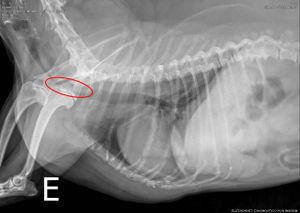

Olá me chamo Valdenis Chuico, eu e minha família precisamos ajudar nosso "Filho Peludo",  Bono! Ele está com 14 anos e precisa de cirurgia, fisioterapia e muitos remédios, que Deus abençoe a todos que puderem ajudar e se não puder, compartilhe, será de grande ajuda. Obrigado!